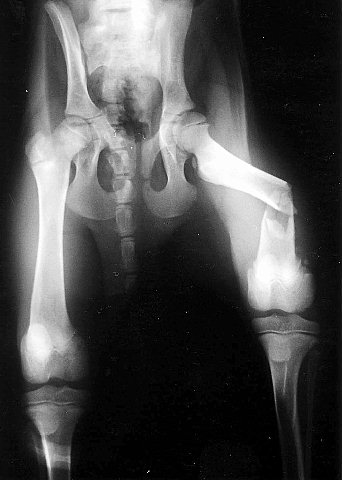

これは向かって右側の骨盤骨折と左側は仙腸関節離断と言います。この場合は仙腸関節を固定することで骨盤の骨折部分は元の位置に戻されて骨が癒合します。

手術から1年後の状態です。横にステンレスのピンをいれてます。本来は専用の長いボルトを使用しますが、この手術の時にはちょうどいいサイズのものがなくピンを代用したわけです。